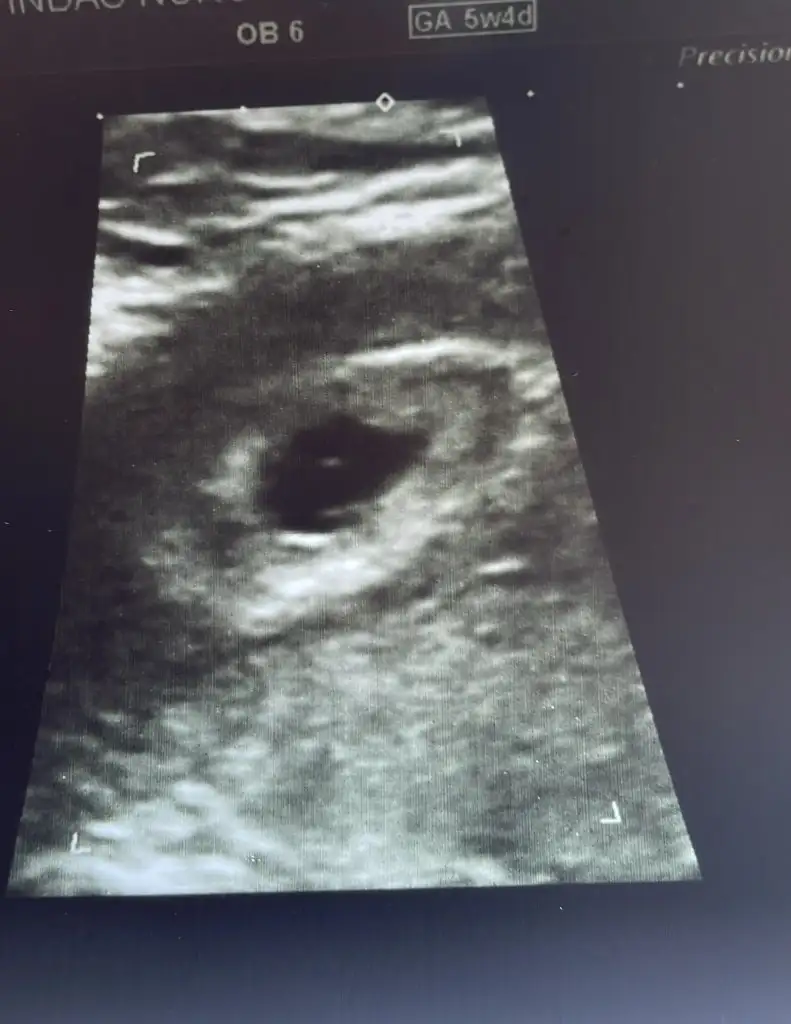

Merhabalar benimkide 5 + 4 karından ultrason tam olarak nasıl bakıldığını anlayamadım ama fikriniz var mı acaba teşekkür ederim

Eklentiler

• A8942186-20CB-41A6-ABE7-0ABA6CC0780D.webp

27,3 KB · Görüntüleme: 60